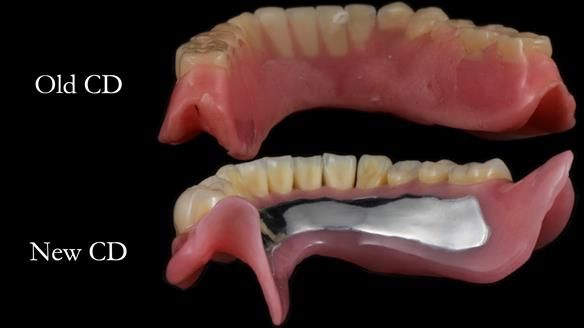

The detailed clinical situation and treatment process are outlined below, with clinical work provided by me and technical work by Rowan Garstang. The treatment spanned 12 months, involving removing 5 upper anterior teeth, adding to an existing upper RPD, followed by creating and fitting metal based complete dentures.